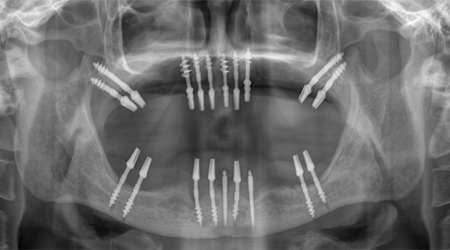

OPG (Full Mouth X-Ray) 500 10

Dental Implant Packages (Lower Jaw)

Technique INR US

8 implants + 14 units Metal-free bridge (Zirconia) 350000 5400

8 implants + 14 units Ceramic bridge (Porcelain fused to metal) 300,000 4500

Dental Implant Packages (Upper Jaw)

10-12 implants including 2 Pterygoid implants + 14 units Metal-free bridge (ZIRCONIA) 400,000 6200

10 implants including 2 Pterygoid implants + 14 units Ceramic bridge (Porcelain fused to metal) 350,000 5500

Full Mouth Rehabilitation with 6-8 Implants Protocol for good bone

Upper Jaw/Lower Jaw (Per Jaw)- NOBEL BIOCARE

6-8 NOBLE BIOCARE Implants + 12 to 14 Units Metal Ceramic Bridge (Porcelain Fused to Metal 350000 5400

6-8 NOBLE BIOCARE Implants + 12 to 14 Units ZIRCONIUM (Metal Free) CERAMIC BRIDGE 500000 7600

Upper Jaw/Lower Jaw (Per Jaw)- ADIN

6-8 ADIN Implants + 12 to 14 Units Metal Ceramic Bridge (Porcelain Fused to Metal) 250000 3800

ALL- ON -4 FOR LESS BONE

Upper Jaw/Lower Jaw (Per Jaw)

4 NOBEL BIOCARE Implants including 2 ANGULATED Implants + IMMEDIATE Provisional Denture + Final Fixed Titanium Hybrid Denture of 12-14 Teeth 350000 5400

4 NOBEL BIOCARE Implants including 2 ANGULATED Implants + IMMEDIATE Provisional Denture + Final Fixed PROCERA Implant Bridge Denture of 12-14 ZIRCONIA Ceramic Crown 500000 7600

ALL- ON -4 WITH ZYGOMA IMPLANTS (FOR MINIMAL BONE)

Upper Jaw

4 NOBEL BIOCARE Implants including 2 ZYGOMA Implants + IMMEDIATE Provisional Denture + Final Fixed TITANIUM HYBRID Denture of 12-14 Teeth 650000 10000

4 NOBEL BIOCARE Implants (QUAD ZYGOMA)+ IMMEDIATE Provisional Denture + Final Fixed TITANIUM HYBRID Denture of 12-14 Teeth 800000 12300